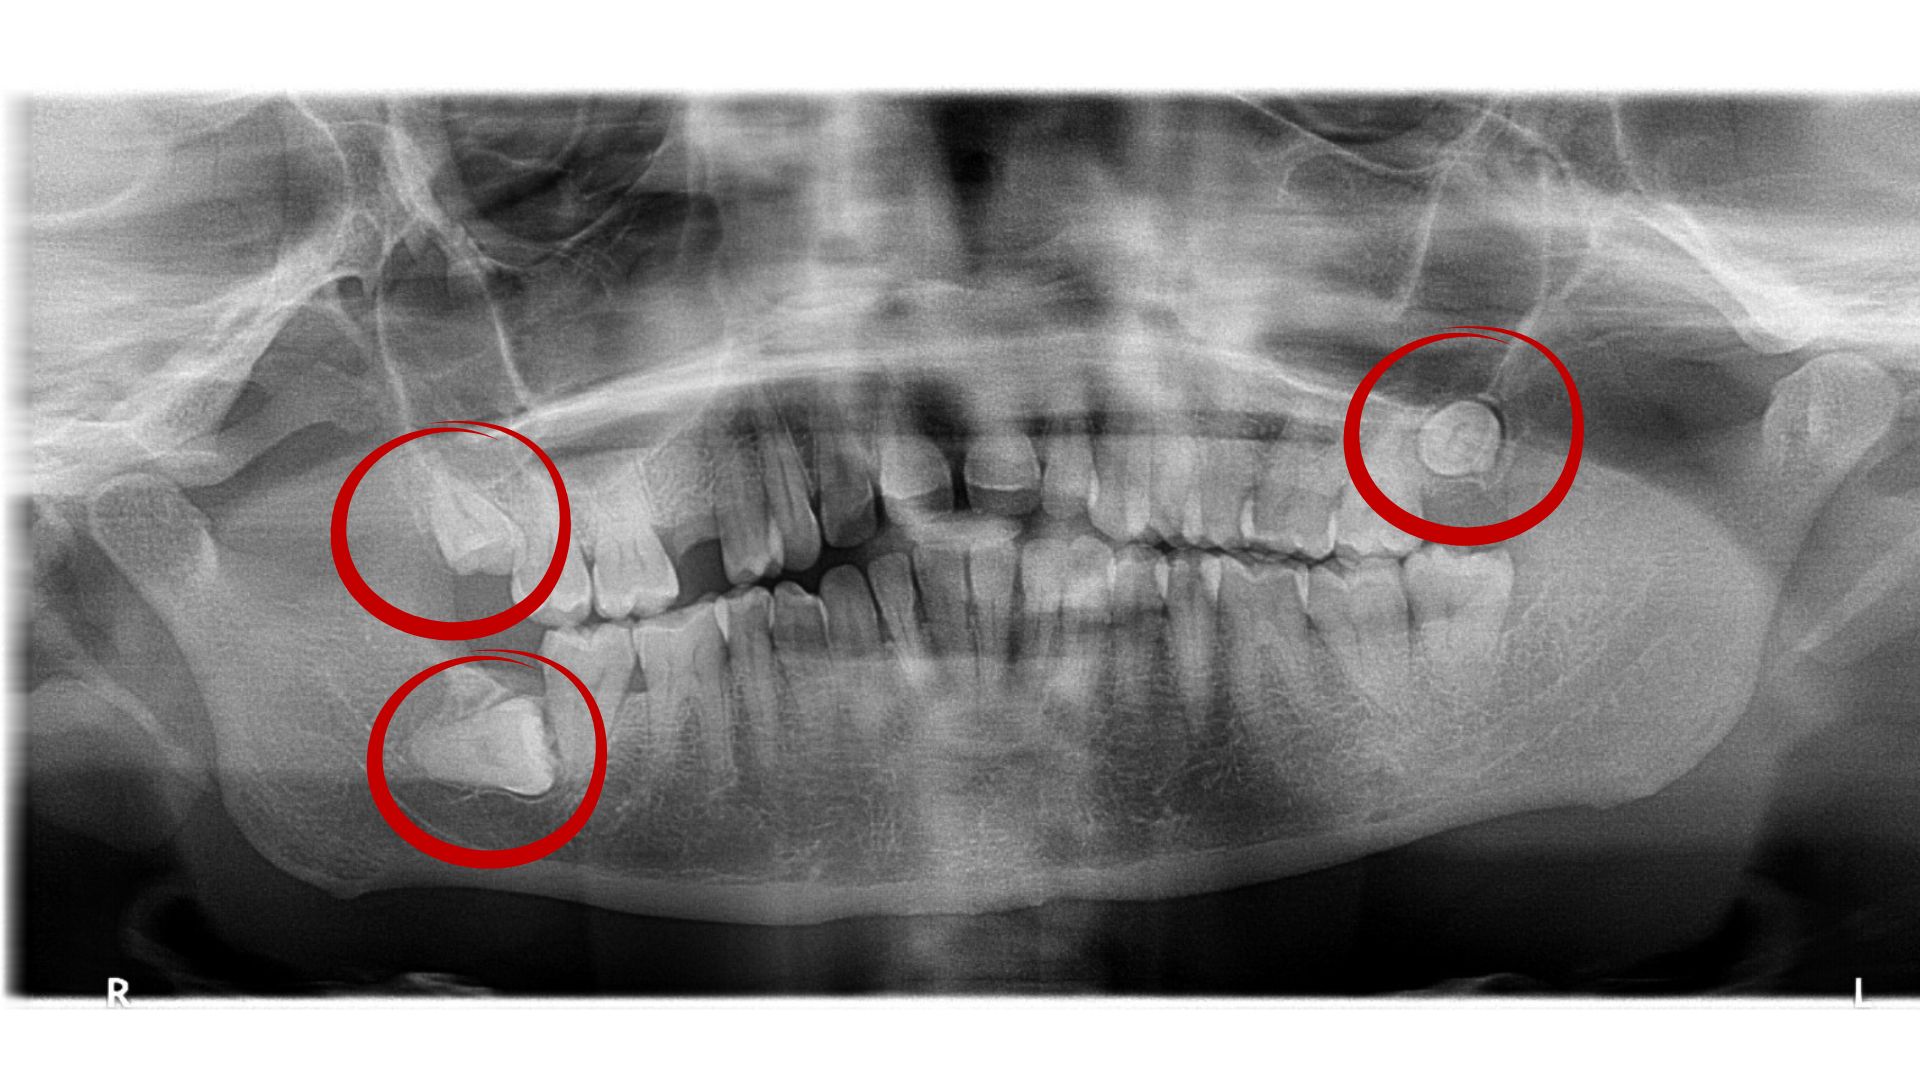

5. Impacted Teeth: Some teeth like wisdom teeth, etc. may not erupt or partially erupt and get stuck in the bone, these teeth are removed by surgical extraction.

2. Surgical Extraction: Surgical extractions are performed when the tooth is not visible in the oral cavity. This is done for badly decayed or broken-down teeth, impacted teeth, teeth associated with cysts and tumors, etc. Stronger pain killers are prescribed by the treating surgeon. The charges for surgical extraction start at Rs 2500 at Dhriti Dental, Hyderabad.

3. Wisdom Tooth Extractions: Wisdom teeth often need extensive surgical procedures to be removed. Our expert oral surgeon provides best pre and post-operative management for wisdom tooth surgeries, ensuring a comfortable experience. The charges for surgical wisdom tooth extractions begin at Rs 4000 at Dhriti Dental, Hyderabad.